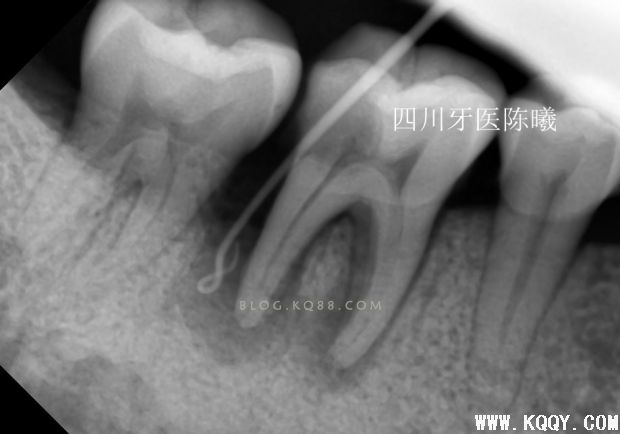

上次根管预备的测长片,当时为了做好就已经在预备后照了试尖片!可惜还是没有料到充填会有这么麻烦!

试尖后发现远颊主尖选择错误,由于是在预备的时候,所以也没有继续试,只是在病人收费票据上写清了个牙根情况!告知患者复诊时带来!(看到这您会问为什么不用病例,因为选择上班的地方都没有写小病例给病人的习惯,所以我也没有写,但是经过这个病例,在考虑以后根管治疗的病人都应该给病人一个病历本了!因为这个问题,成了造成后面问题的原因之一)

试尖完发现近中稍欠,远中颊根部到位,于是用20#25#K挫稍微挫了下根尖3分之1,远颊根挫时病人告知有疼痛,依然没有重视,在冲洗的时候发现少许没有去除干净的氢氧化钙糊剂从根管内溢出,又是一个问题,这下觉得应该到位了,那就充填吧,于是用试尖的牙胶尖号数充填,结果如下

从这3张片子上可以看出近远中都有超填,唉,重来吧!(发博客都一波三折,这都第四次编辑了,不容易啊)跟病人说清楚情况取得同意后,准备重新充填,但是这个时候不知道近远中超填的是颊根还是舌根,又一个问题,只有想办法,我去掉近远中颊根充填物后照片(远中充填得很密合,废好大功夫才取出来)

可以看出在取出近远中颊根充填物后,远中依然超填,说明远中超填的是舌根,然后觉得近中舌根充填锥度也不连续,干脆全部取出重新做!

这次留个后路,把刚才超填的牙胶去掉头部1MM,然后保留大部分牙胶,紧密充填后拍片!,终于感觉及格了,还是多角度看看

进一步确定感觉没有大问题了,终于可以告诉患者根充结束了,由于反复操作,时间过长,担心出问题,病人也在考虑要不要做修复体,所以最后暂封上部观察